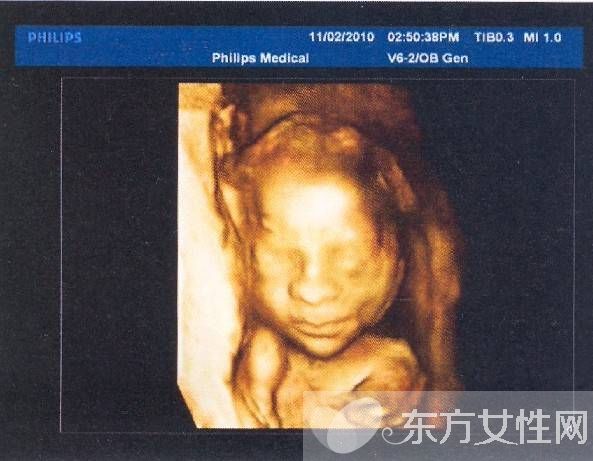

普通B超和彩色B超都是二維平面圖像,這兩種技術(shù)仍在使用,但由于觀測效果較為依賴羊水量和胎兒體位,一旦在懷孕晚期羊水減少或者胎兒面向母親的背部,觀測效果就不太理想。而且,二維圖像不能滿足準(zhǔn)媽媽們“看到”寶寶模樣的愿望。因此,最近幾年,隨著計算機技術(shù)的發(fā)展,又出現(xiàn)了三維B超,也就是將二維圖像合成模型,透過屏幕可從各個方位觀察胎寶寶。

三維彩超、四維彩超的圖像是后期生成的,并不是說觀察到的圖像就是三維、四維的,而是仍然用普通彩超觀察,然后通過儀器中的轉(zhuǎn)換軟件將觀察到的平面圖像轉(zhuǎn)成三維、四維的立體圖像,使不懂B超圖像的人也能看出胎兒的模樣。而三維和四維的區(qū)別就在于在一個“時間維”,也就是說,前者是圖片,后者是錄像,可以讓孕媽媽看到胎兒一連串的動作。